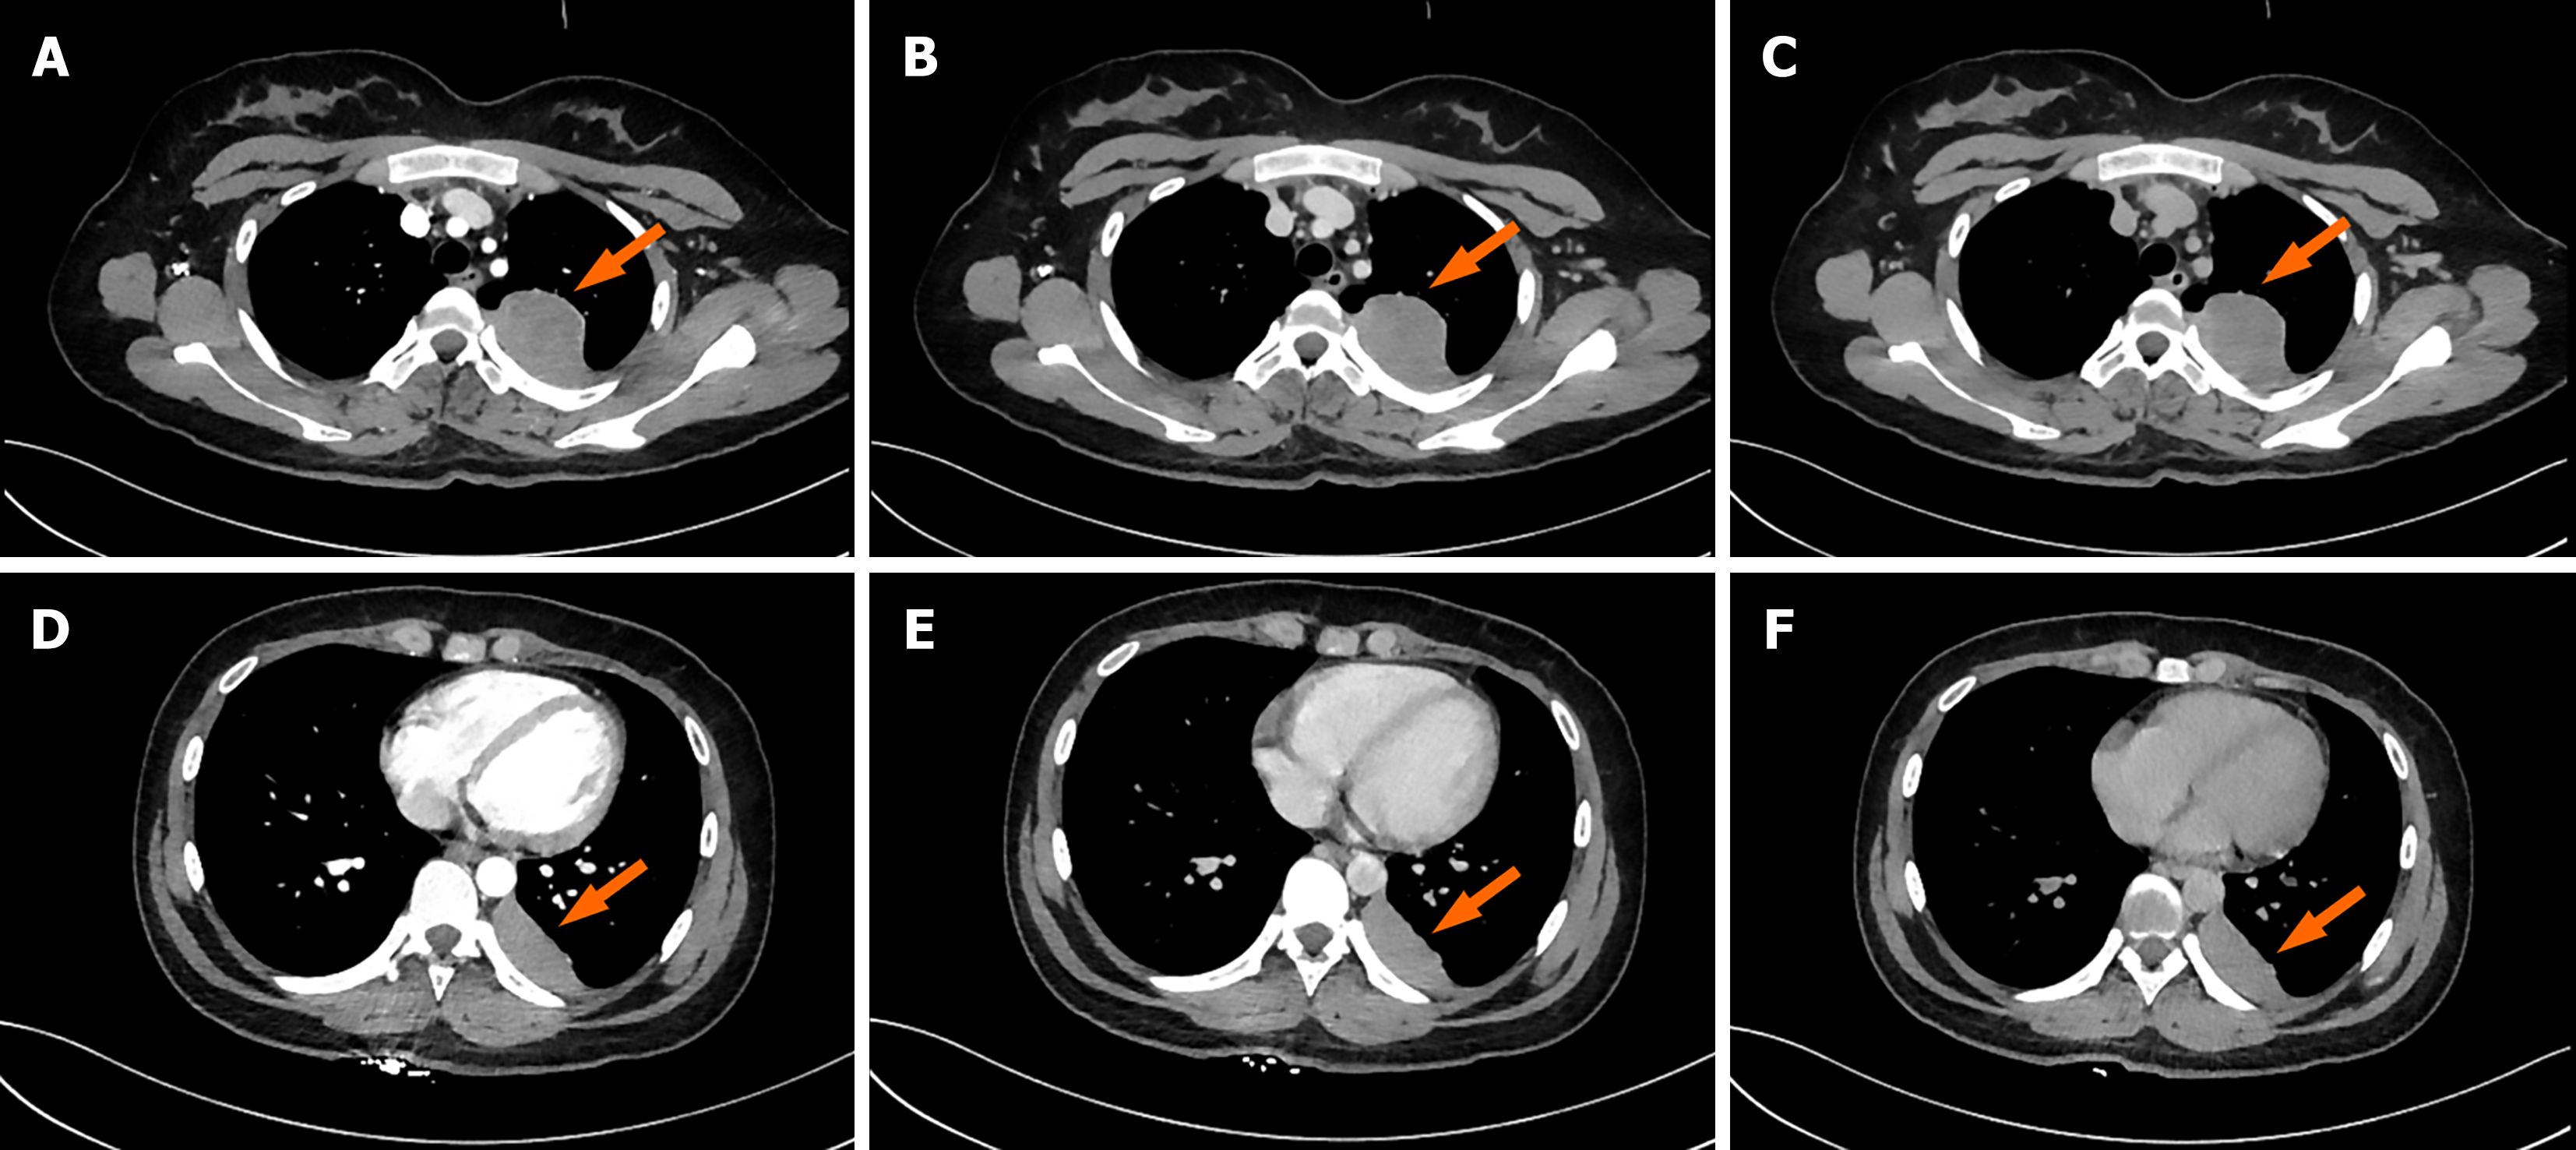

Figure 2 Chest triphasic contrast-enhanced images.

Lesion 1: A: Arterial phase; B: Venous phase; C: Delayed phase. Lesion 1 (arrow) demonstrated triphasic contrast-enhanced computed tomography values of 61 HU, 63 HU, and 59 HU in the arterial, venous, and delayed phases, respectively. Lesion 2: D: Arterial phase; E: Venous phase; F: Delayed phase. Lesion 2 (arrow) showed enhancement values of 61 HU, 69 HU, and 64 HU across the corresponding phases.